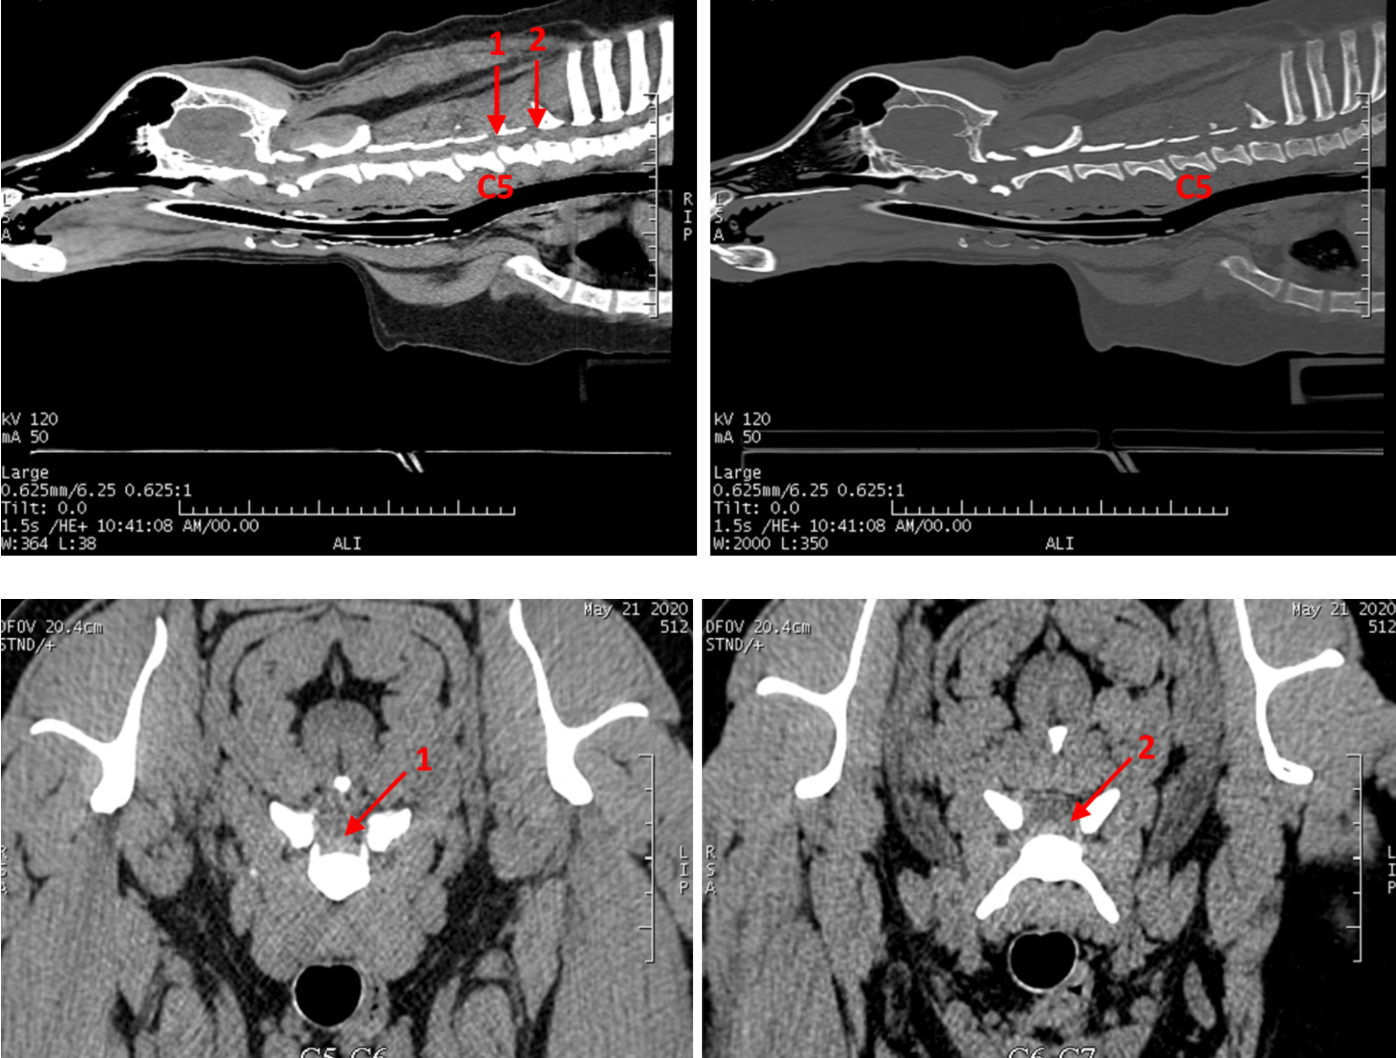

O que é?

O síndrome de cauda equina também designado por estenose degenerativa lombo-sagrada é uma apresentação patológica localizada entre L7 e o sacro que pode envolver vários problemas como herniação discal, subluxação de S1, anomalias vertebrais ou sacrais e compromisso vascular

Como se diagnostica/sinais?

Os sinais que nos levam a suspeitar desta doença são dor na região lombo-sacra, claudicação, presença de défices neurológicos motores, incontinência urinária/fecal e perda de força na cauda.

O paciente poderá apresentar quadros com diferentes gravidade, sendo os sinais clínicos desde subtis a muito evidentes.

O diagnóstico é feito por meio de estudo radiográfico, onde são detetadas lesões ósseas compatíveis com a patologia referida.

Após realização de estudo radiográfico o paciente será submetido a um estudo de imagem avançada (TAC ou ressonância) para compressão do grau de compressão medular existente.

Qual o tratamento indicado?

Os quadros ligeiros podem ser tratados de forma conservativa onde é aconselhado o repouso em jaula durante um período de 2 a 6 semanas e é dado suporte farmacológico para maneio de dor.

Caso o paciente apresente um quadro sintomatológico refratário ao tratamento conservativo ou com um grau de compressão significativo a nível medular é realizado tratamento cirúrgico. O tratamento cirúrgico consiste na laminectomia dorsal para descompressão da medula espinal podendo ser associado (conforme a apresentação da doença) a fusão vertebral entre L7 e S1.